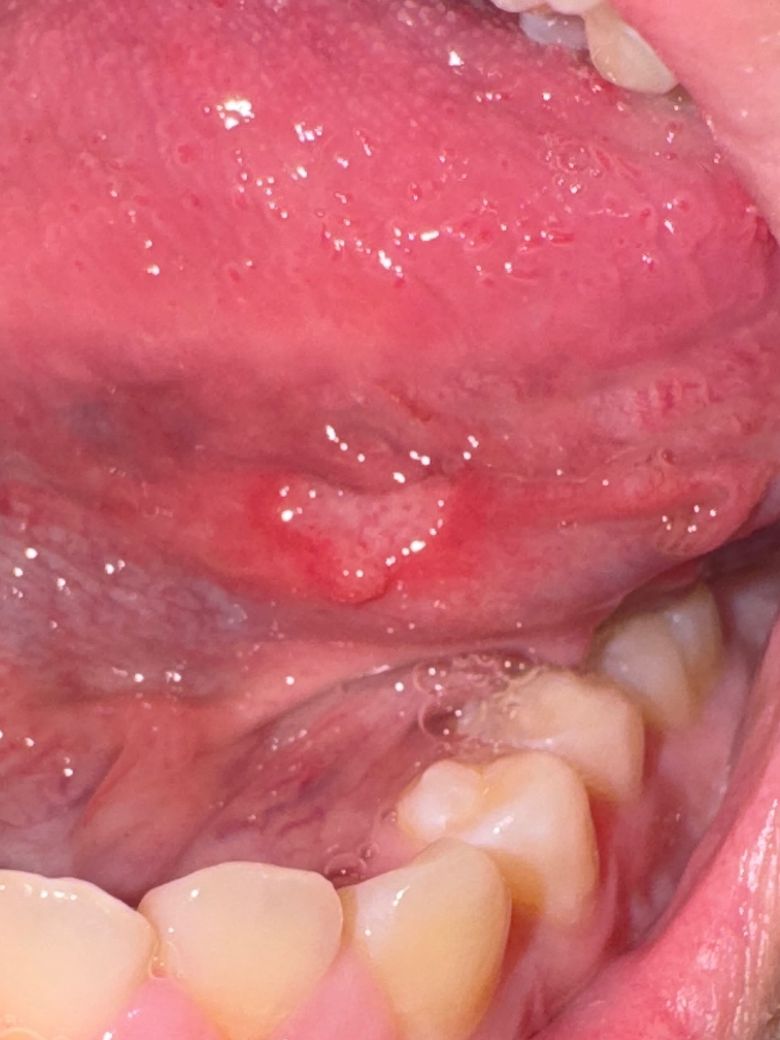

너무 아프고 구내염처럼 동그란?게 아니고

제가 많이 마는 구내염처럼 좀 정직한 동그라미가 아니고

저런 모양인데 다른병은 아니겠죠... ㅠㅠㅠㅠ

아프타성 구내염의 경우 크기가 큰 경우 대아프타성 구내염도 있습니다 경과를 좀 지켜보면 좋을 것 같습니다